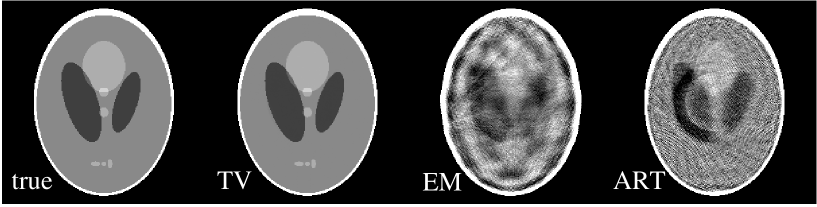

Another omni-present physical factor that contributes to data inconsistency is signal noise in the projection measurements. It is of practical significance to evaluate the performance of the TV algorithm in the presence of data noise. While a thorough evaluation of the noise properties of the TV algorithm is beyond the scope of this work, we present preliminary results indicating that the TV algorithm appears to be effective on sparse data problems even when the data contain inconsistencies due to signal noise. For the noise studies, we again take the few-view and bad-bin cases in Secs. III.1 and III.3. In each case, Gaussian noise is introduced in the projection data at the level of 0.1 of the ideal measurement values.

For the few-view study, we show in Fig. 13 images reconstructed by use of the TV (labeled TV1 and TV2), EM, and ART algorithms. The iteration numbers for the TV, EM and ART images are 200, 200, and 100, respectively. In the studies with consistent data above, the differences between the TV1 and TV2 images were numerically negligible. With inconsistencies resulting from data noise, however, there is a marked difference. The image after the gradient descent phase is clearly a regularized version of the image obtained after the data projection and positivity constraint. Depending on the task, either image may prove useful for a particular imaging application. For the few-view study, both images and obtained with the TV algorithm appear to have less artifacts than the EM and ART reconstructions in Fig. 13. We point out again that no explicit regularization is performed with EM or ART in the studies here and below aside from the fact that we truncate the iteration numbers at 200 and 100 in the EM and ART algorithms, respectively.

For the bad bin case, we generated noisy data by adding Gaussian noise, at the level of 0.1% of the individual true data values, to the noiseless data described in Sec. III.3. In Fig. 14, we show images reconstructed by use of the TV algorithm (TV1) and (TV2), the EM, and the ART algorithm. The iteration numbers for the TV, EM, and ART images are 200, 200, and 100, respectively. Again, we show two TV images in Fig. 13: TV1 and TV2. The results of this study suggests that the TV and EM algorithms can still effectively correct for the effect of the missing detector bins. The ART algorithm, which showed very mild streaking in Fig. 9 under the ideal condition, displays significant streaking due to the combination of signal noise and bad detector bins.